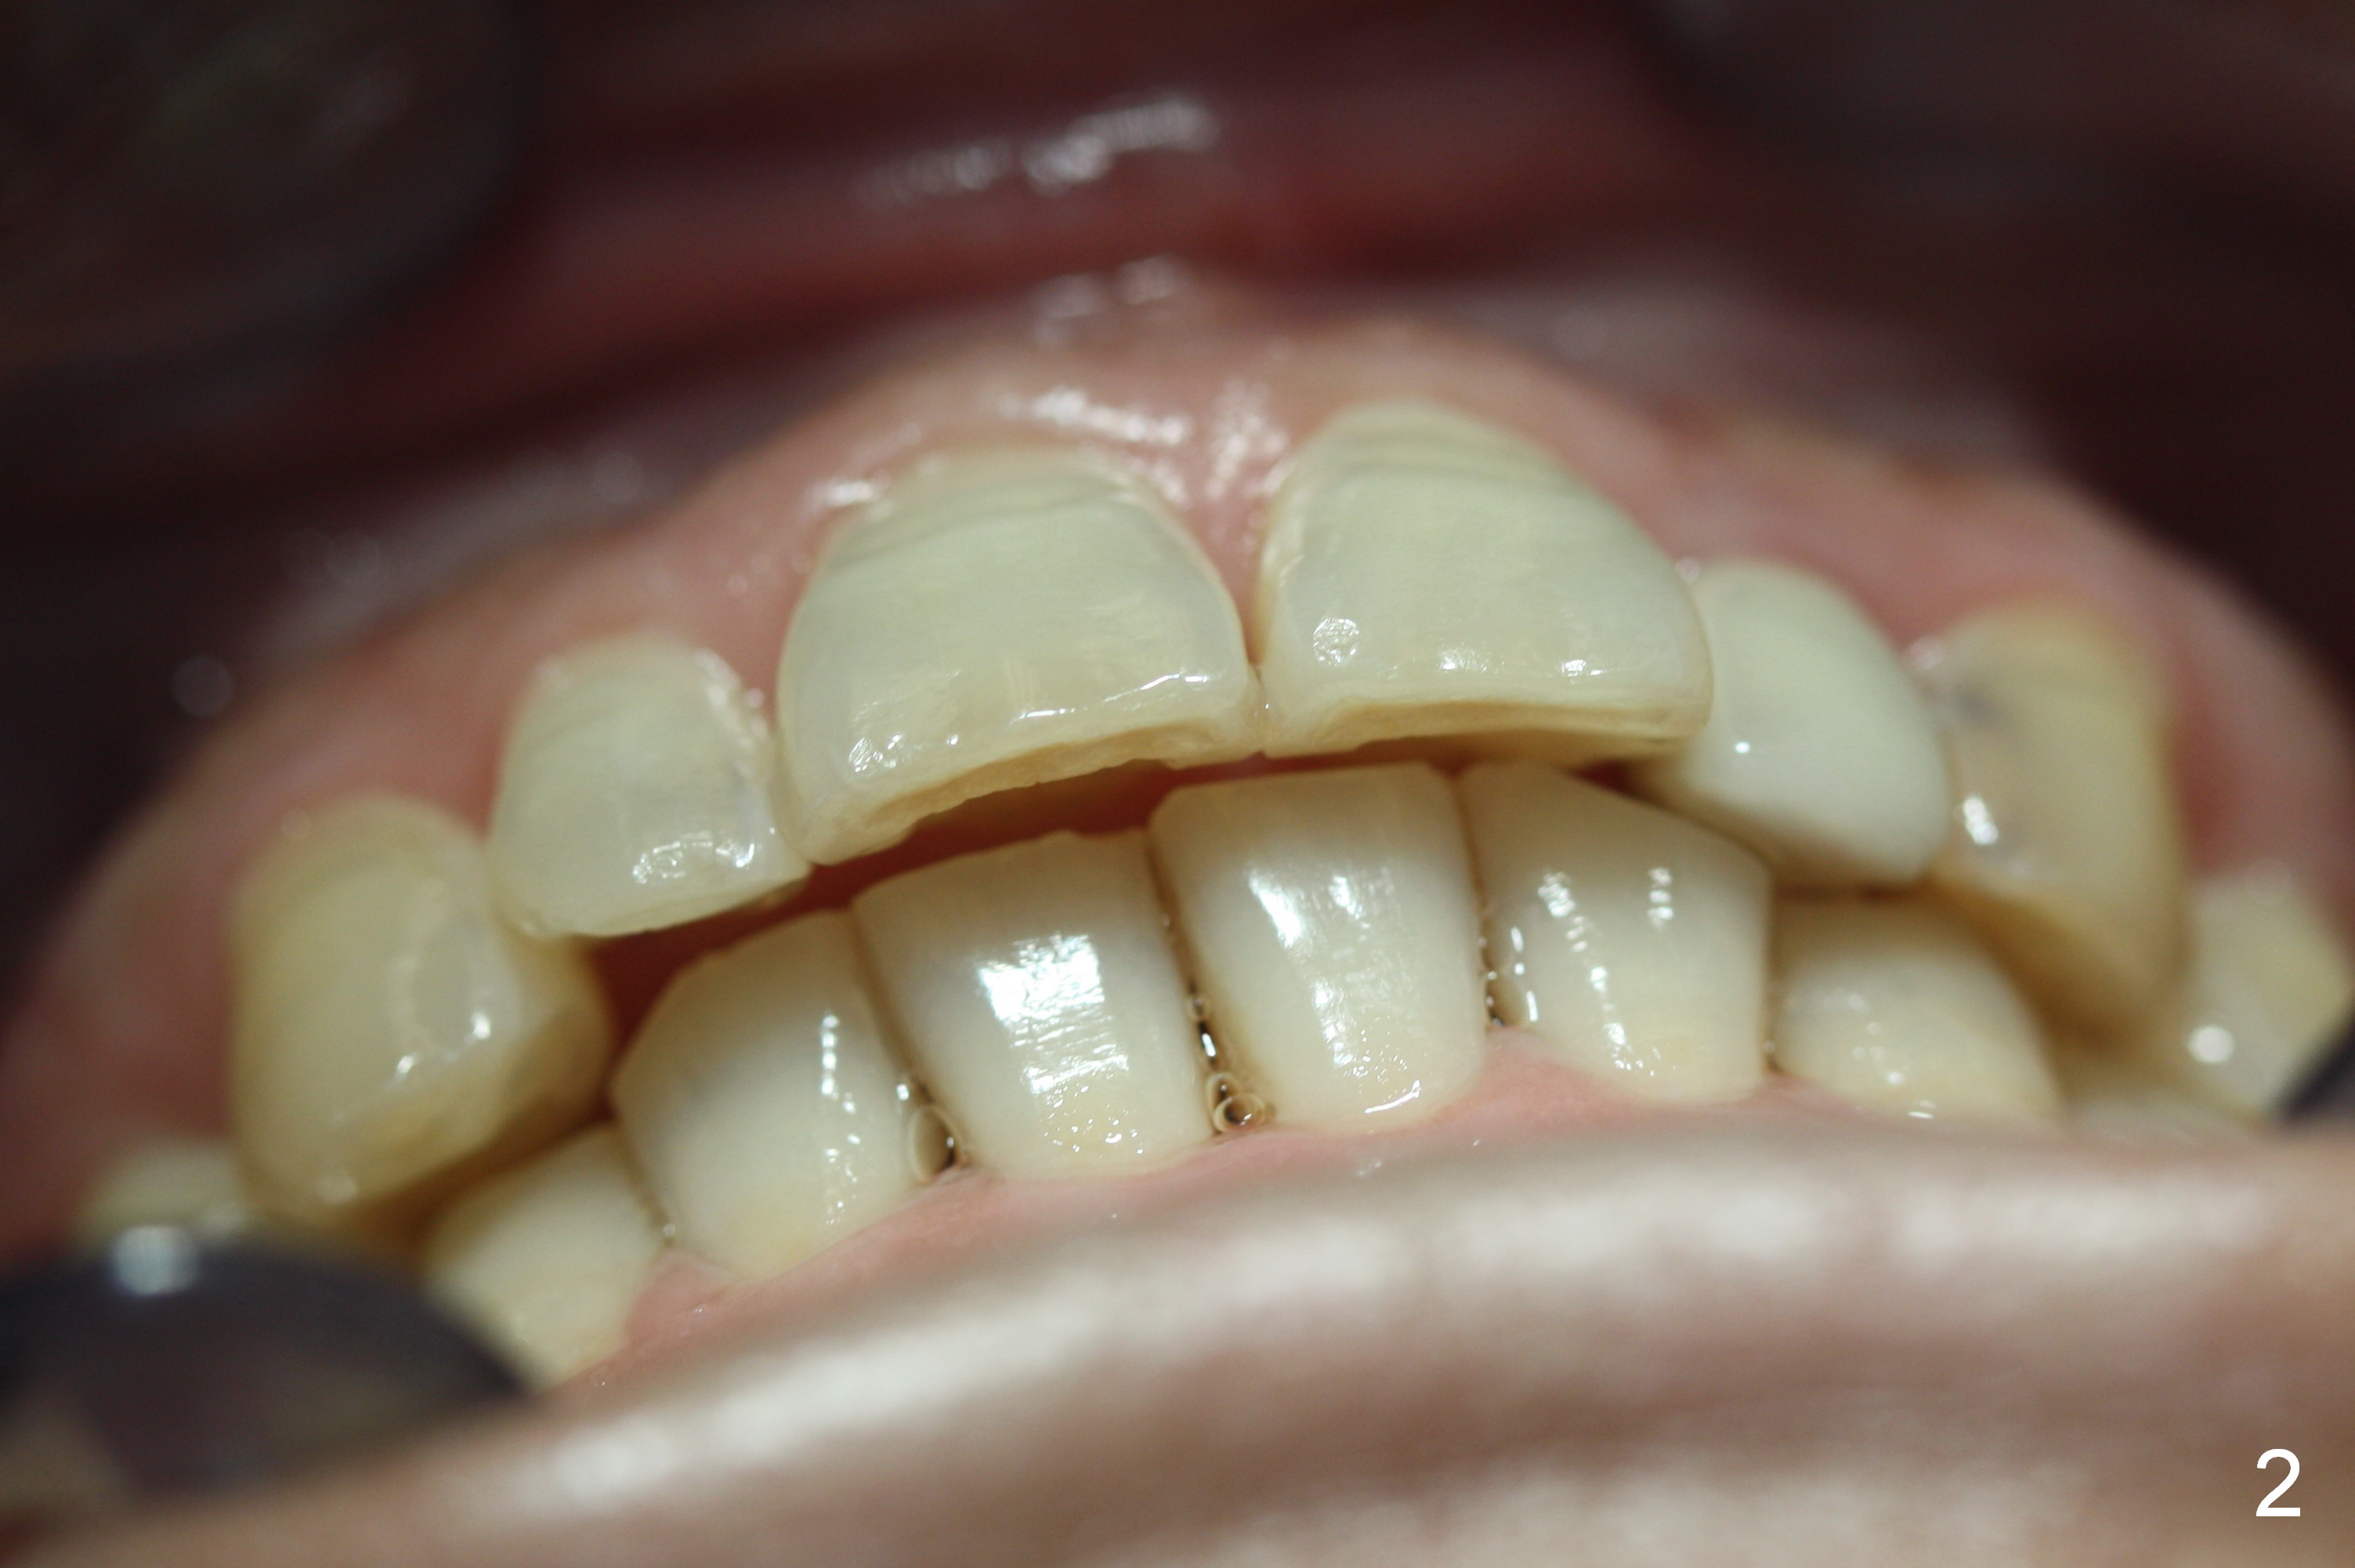

A 53-year-old woman wants to improve tooth appearance. Her concerns include microdontia at UR, UL 2 and caries at UL 3. The upper dental midline deviates to the left (Fig.1), while the lower one to the right (Fig.2). This may be related to unilateral Class II malocclusion (Fig.3,4).